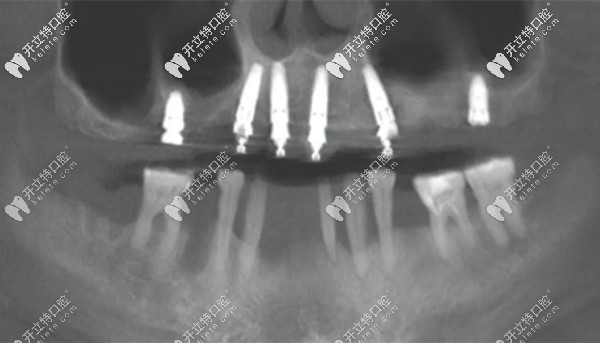

點(diǎn)種6顆種植體

(上頜點(diǎn)種六顆種植體)

能看懂么?這張全景片中的上頜六顆種植體,就是“點(diǎn)種”技術(shù)。分別選取牙槽骨量較為充沛的部位,將牙根種入。

兩側(cè)后牙可以明顯看出,用的是較短的種植體,這樣的好處是可以避免植骨手術(shù)。